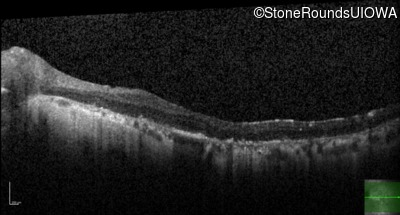

Optical Coherence Tomography - Left - 20/70

Exemplar / OCT Stack